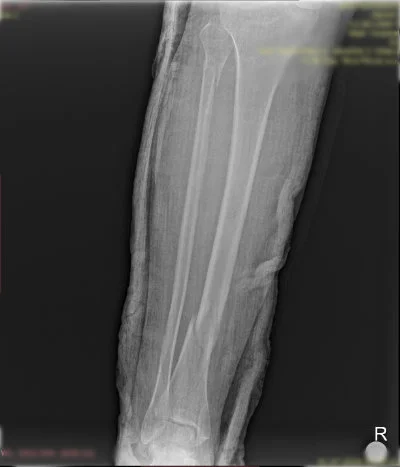

Görüntüleri büyütmek için resmin üstüne tıklayınız.